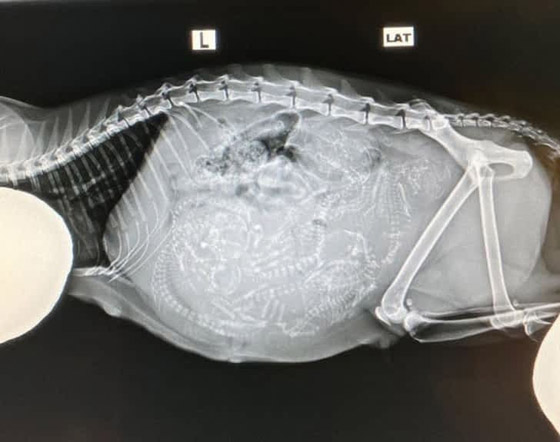

أشعة سينية حيوانية

النهاية مع تلك الصورة التي تكشف عن أشعة سينية لكنها لا تخص بشرا، بل لقطة في مرحلة الحمل.